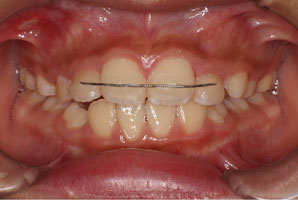

こちらの初診(男性)の患者さんは、開咬合 / 叢生歯列の症状がありました。

1期治療 8歳9ヶ月 2期治療 12歳4ヶ月から治療を開始し、1期治療 7ヶ月 2期治療 2年5ヶ月の間、スタンダードエッジワイズ法(与五沢エッジワイズシステム)を用い矯正治療を行いました。

| 治療開始年齢 | 1期治療 8歳9ヶ月 2期治療 12歳4ヶ月 | |||||||||||||||||||||||||||||||||||||||||||||||||||||||||||

| 症例分類 | 開咬合 / 叢生歯列 / 偏位咬合 | |||||||||||||||||||||||||||||||||||||||||||||||||||||||||||

| 8歳9ヶ月 | 9歳8ヶ月 | |